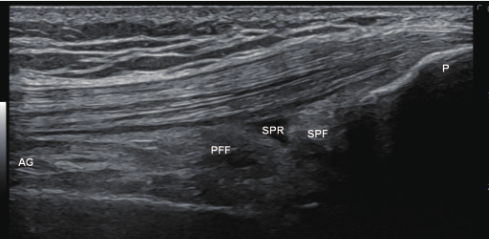

초음파로 보는 알짜근육학, 319p

위 사진은 제가 집필한

영상입니다.

한의학의 음시, 양구혈을

초음파로 관찰하면

대퇴사두근 슬개골 부착부와

관절낭과 연결된 주머니(recess)가

이렇게 정상적으로 보여야 합니다.

양구혈의 경혈 초음파 영상